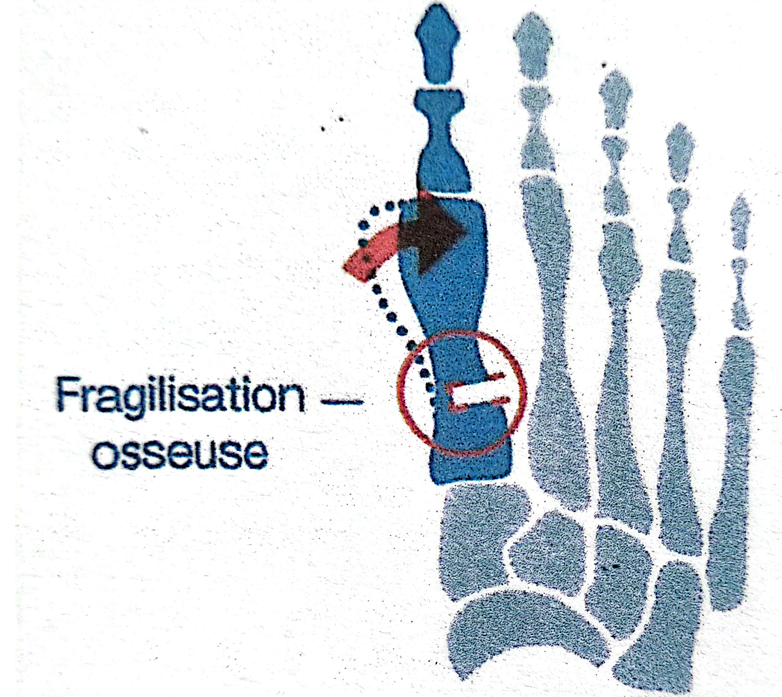

Figure 6 : La correction axiale percutanée, est réalisée par une mèche-fraise de Shanonn, introduite par une incision de 2 à 3mm et qui effectue une « fragilisatiuon osseuse « au niveau métaphysaire, laissant un pont osseux . Puis par une « manœuvre manuelle » externe, le chirurgien exerce une pression externe qui se fait du pont osseux qui agit comme une chanrière pour corriger de quelques degrés la dévéiation axiale .

L’approche percutanée présente plusieurs avantages. ( figure 6) Les incisions cutanées sont très petites, ce qui réduit la taille des cicatrices et limite l’agression des tissus mous. Cette approche peut également contribuer à diminuer la douleur postopératoire et à faciliter la récupération fonctionnelle, tout en permettant une correction précise de la déformation.